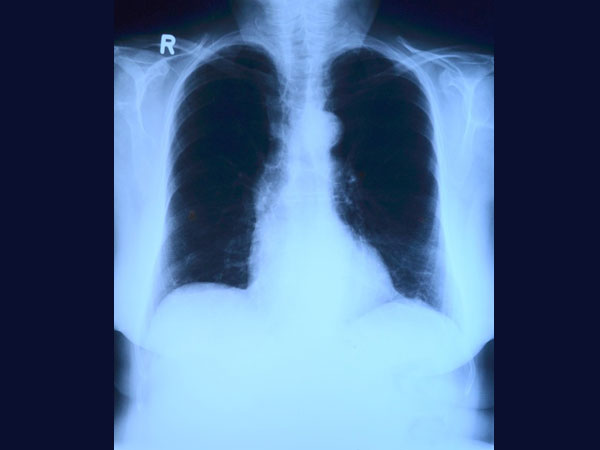

ब्लड टेस्ट और एक्स-रे की मदद से इसका पता लगाया जाता है। इलाज के लिए सूजन दूर करने वाली दवाएं और आइस थैरेपी की जाती है। कैल्शियम के कारण डैमेज अधिक होने पर सर्जरी की जाती है।